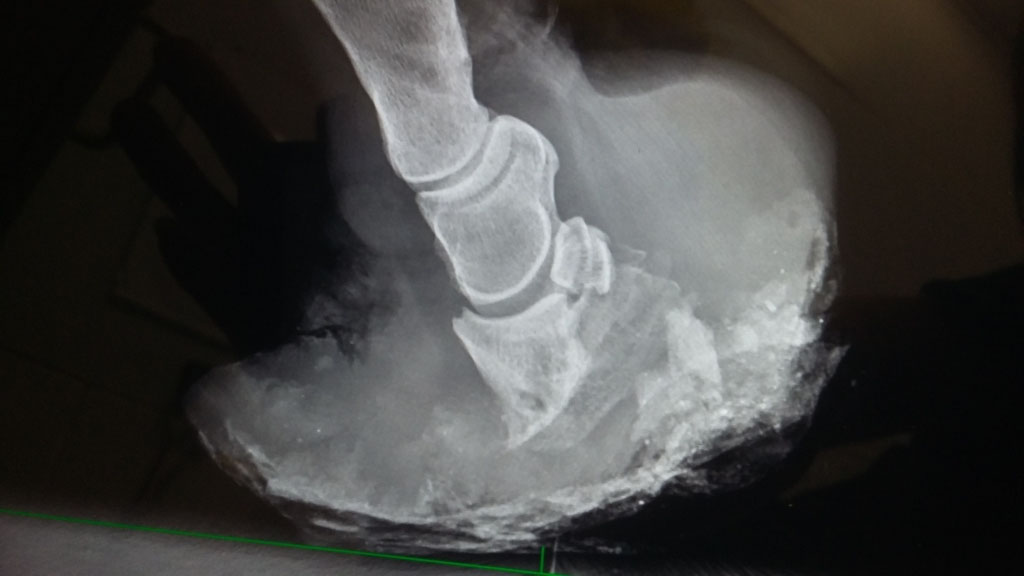

What’s actually going on in the foot of an animal with laminitis is still little understood. Several papers focus on lamellar lesions. Others look at the role that growth factor receptors may play in the disease.